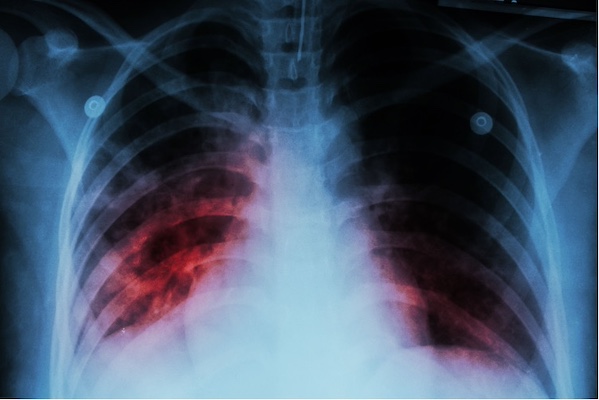

强生公司旗下的杨森制药公司(janssen)宣布已向欧洲药品管理局(ema)提交了贝达喹啉(sirturo)的ii类变异申请,该药作为联合疗法的一部分,适用于五岁以上的成人和儿童耐多药结核分枝杆菌肺结核(tb)患者。今年 8 月,该药还向 fda 提交了补充新药申请(snda)。

sirturo 是一种二芳基喹啉类抗结核药物,适用于肺 mdr-tb 成人患者的联合治疗。美国食品及药物监督管理局指出,sirturo 应仅用于无法以其他方式提供有效治疗方案的病例。